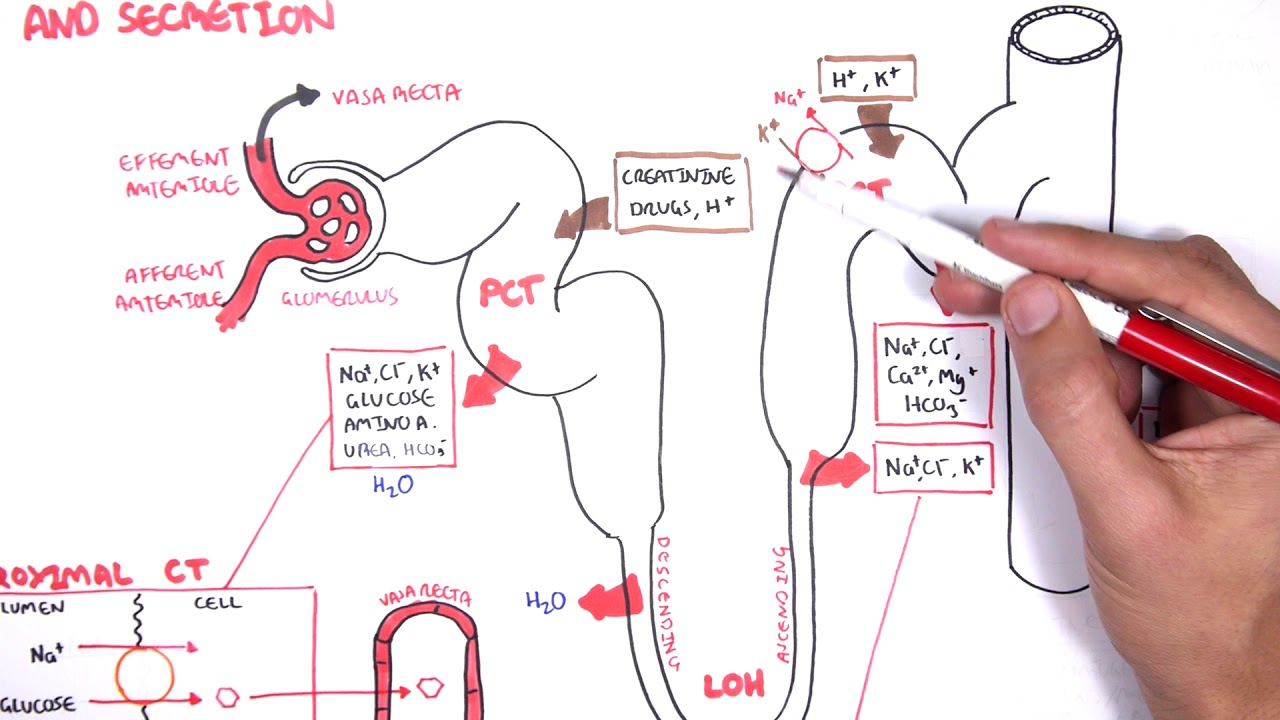

The kidneys monitor and regulate the levels of hydrogen ions h and bicarbonate ions in the blood to control blood ph. Glomerular filtration glomerular filtration is the renal process whereby fluid in the blood is filtered across the capillaries of the glomerulus. The right kidney is lower than the left due to displacement by the liver.

Nephrology Physiology Reabsorption And Secretion

Nephrology Physiology Reabsorption And Secretion